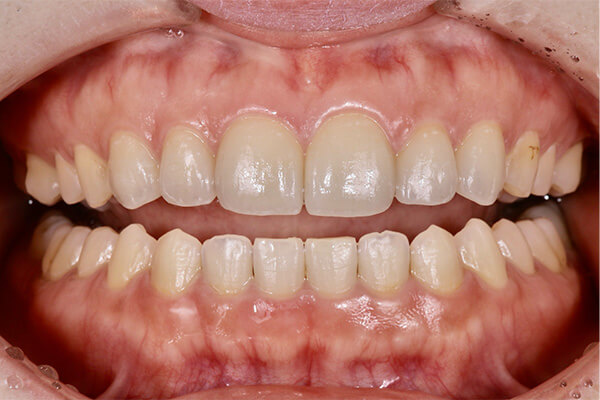

上の前歯の古い被せ物を治したいと言うことで来院されました。上下の前歯は少しガタガタになっており、奥歯には古い金属の詰め物が見られます。

上の前歯の被せ物が長い期間保つようにするためには、下の前歯のガタガタを整えておく必要があります。この症例くらいのガタガタであれば、インビザラインGoを使えば短期間で綺麗に治すことができます。歯並びが整ったことで治療のモチベーションが上がり、ホワイトニングと奥歯の銀歯を全てセラミックに置き換える治療を行い、金属がない(ノンメタル)状態になりました。